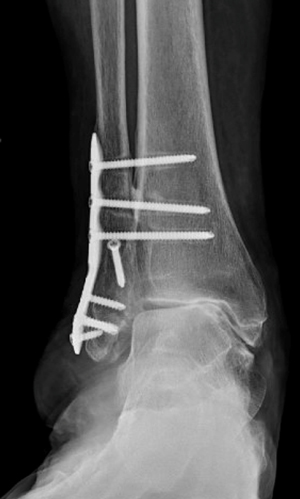

TOTAL ANKLE REPLACEMENT :: ORIF CALCANEUS :: ORIF ANKLE FRACTURE DISLOCATION :: COMPLEX BUNION AND LESSER TOE CORRECTION :: TALUS FRACTURE -1 :: TALUS FRACTURE -2 :: LISFRANC REPAIR :: COMPLEX TRIPLE ARTHRODESIS 1 :: COMPLEX TRIPLE ARTHRODESIS 2 :: MINIMALLY INVASIVE BUNION REPAIR 1 :: MINIMALLY INVASIVE BUNION REPAIR 2 :: ARTHROSCOPIC CARTILAGE REPAIR :: TENEX SPUR DEBRIDEMENT :: Haglunds Debridement and Achilles Repair